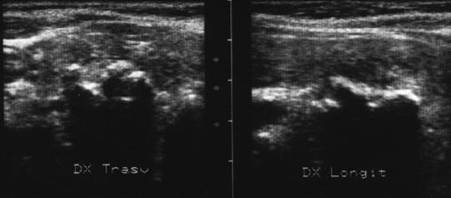

Lob drept , proiectie trasversala si longitudinala.

Femeie 19 ani. Leziune marcant hipoecogen cu intarire posterioara, de 16x20x26mm (4 cc) in lobul drept.

Examen citologic: macrofagi, fara tireocite.